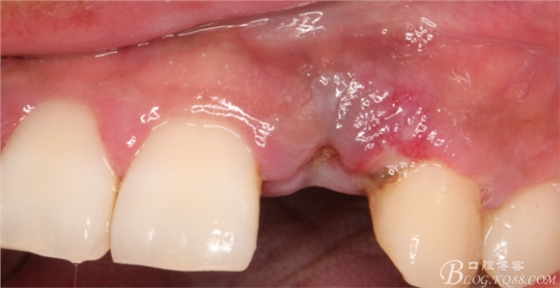

10天拆線一切正常,又過了兩周患者復(fù)診,自述期間無異常??趦?nèi)檢查,真的嚇了一跳,唇側(cè)鼓了個(gè)包,擠壓有白色分泌物溢出,絕對不是膿液,液體排除后,術(shù)區(qū)觸診空虛,外觀塌陷。這時(shí)候考研大夫的時(shí)刻到了,是先觀察一段時(shí)間再說?還是馬上進(jìn)行處理?我的回答是:馬上處理!如果你沒有及時(shí)處理,而是放患者回家觀察,那么接下來會(huì)發(fā)生如下情況:1.回家后患者家屬及親友會(huì)有很多你可以想象得到的討論;2.患者及家屬會(huì)對你產(chǎn)生不信任,勢必會(huì)到其他門診或醫(yī)院檢查,他院大夫會(huì)不會(huì)發(fā)表對你不利的言論;3甚至?xí)蚁嚓P(guān)法律界人士找你討要說法。

于是我果斷告知患者,手術(shù)失敗了,不能拖延,如不及時(shí)處理,炎癥繼續(xù)發(fā)展會(huì)很快波及鄰牙牙槽骨。患者接受我的建議。切開翻瓣,骨粉及生物膜消失了,骨吸收嚴(yán)重,幸運(yùn)的是,因?yàn)樘幚砑皶r(shí),鄰牙骨支持依然存在。